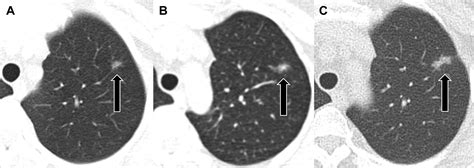

A ground glass nodule (GGN) refers to a hazy, cloudy opacity within the lungs that appears on a CT scan. Unlike solid nodules, which are dense enough to completely obscure the underlying lung tissue, a GGN allows the structures of the lung, such as the airways and blood vessels, to remain visible through the haze. The term derives from the visual similarity to glass that has been treated to appear frosted or translucent.

• Consistency: Whether the nodule is "pure" (completely hazy) or "part-solid" (containing a denser core).

Pure Ground Glass Uniformly hazy, < 5mm Usually monitor annually

Pure Ground Glass Uniformly hazy, > 5mm Short-interval CT follow-up

Part-Solid Nodule Contains a solid component Closer monitoring or biopsy